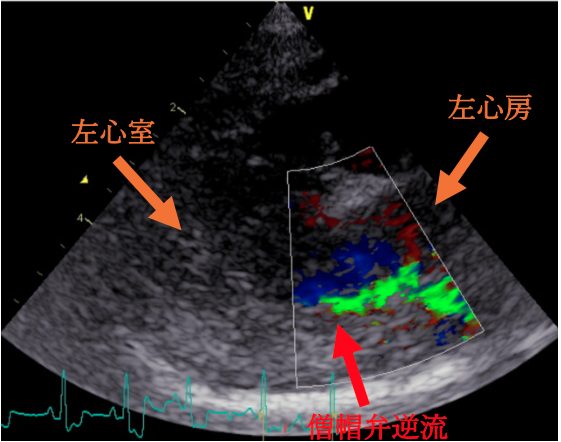

<心臓超音波検査結果>

今回の⼼臓超⾳波検査では、僧帽弁からの⾎液の逆流は認められるものの、⼼臓のサイズの拡⼤や負荷の増加は認められませんでした。そのため、現在の治療(強⼼薬・⾎管拡張薬など)を継続しながら経過観察となりました。

わんちゃんの⼼臓は、右⼼房/右⼼室・左⼼房/左⼼室という 4 つの部屋からできています。それぞれの間には⾎液が逆流しないように「弁」があります。そのうち、左⼼房と左⼼室を隔てているのが「僧帽弁」です。

粘液腫様僧帽弁疾患とは、この僧帽弁がしっかり閉まらなくなり、⾎液が逆流してしまう病気です。初期には症状が出ないこともありますが、進⾏すると